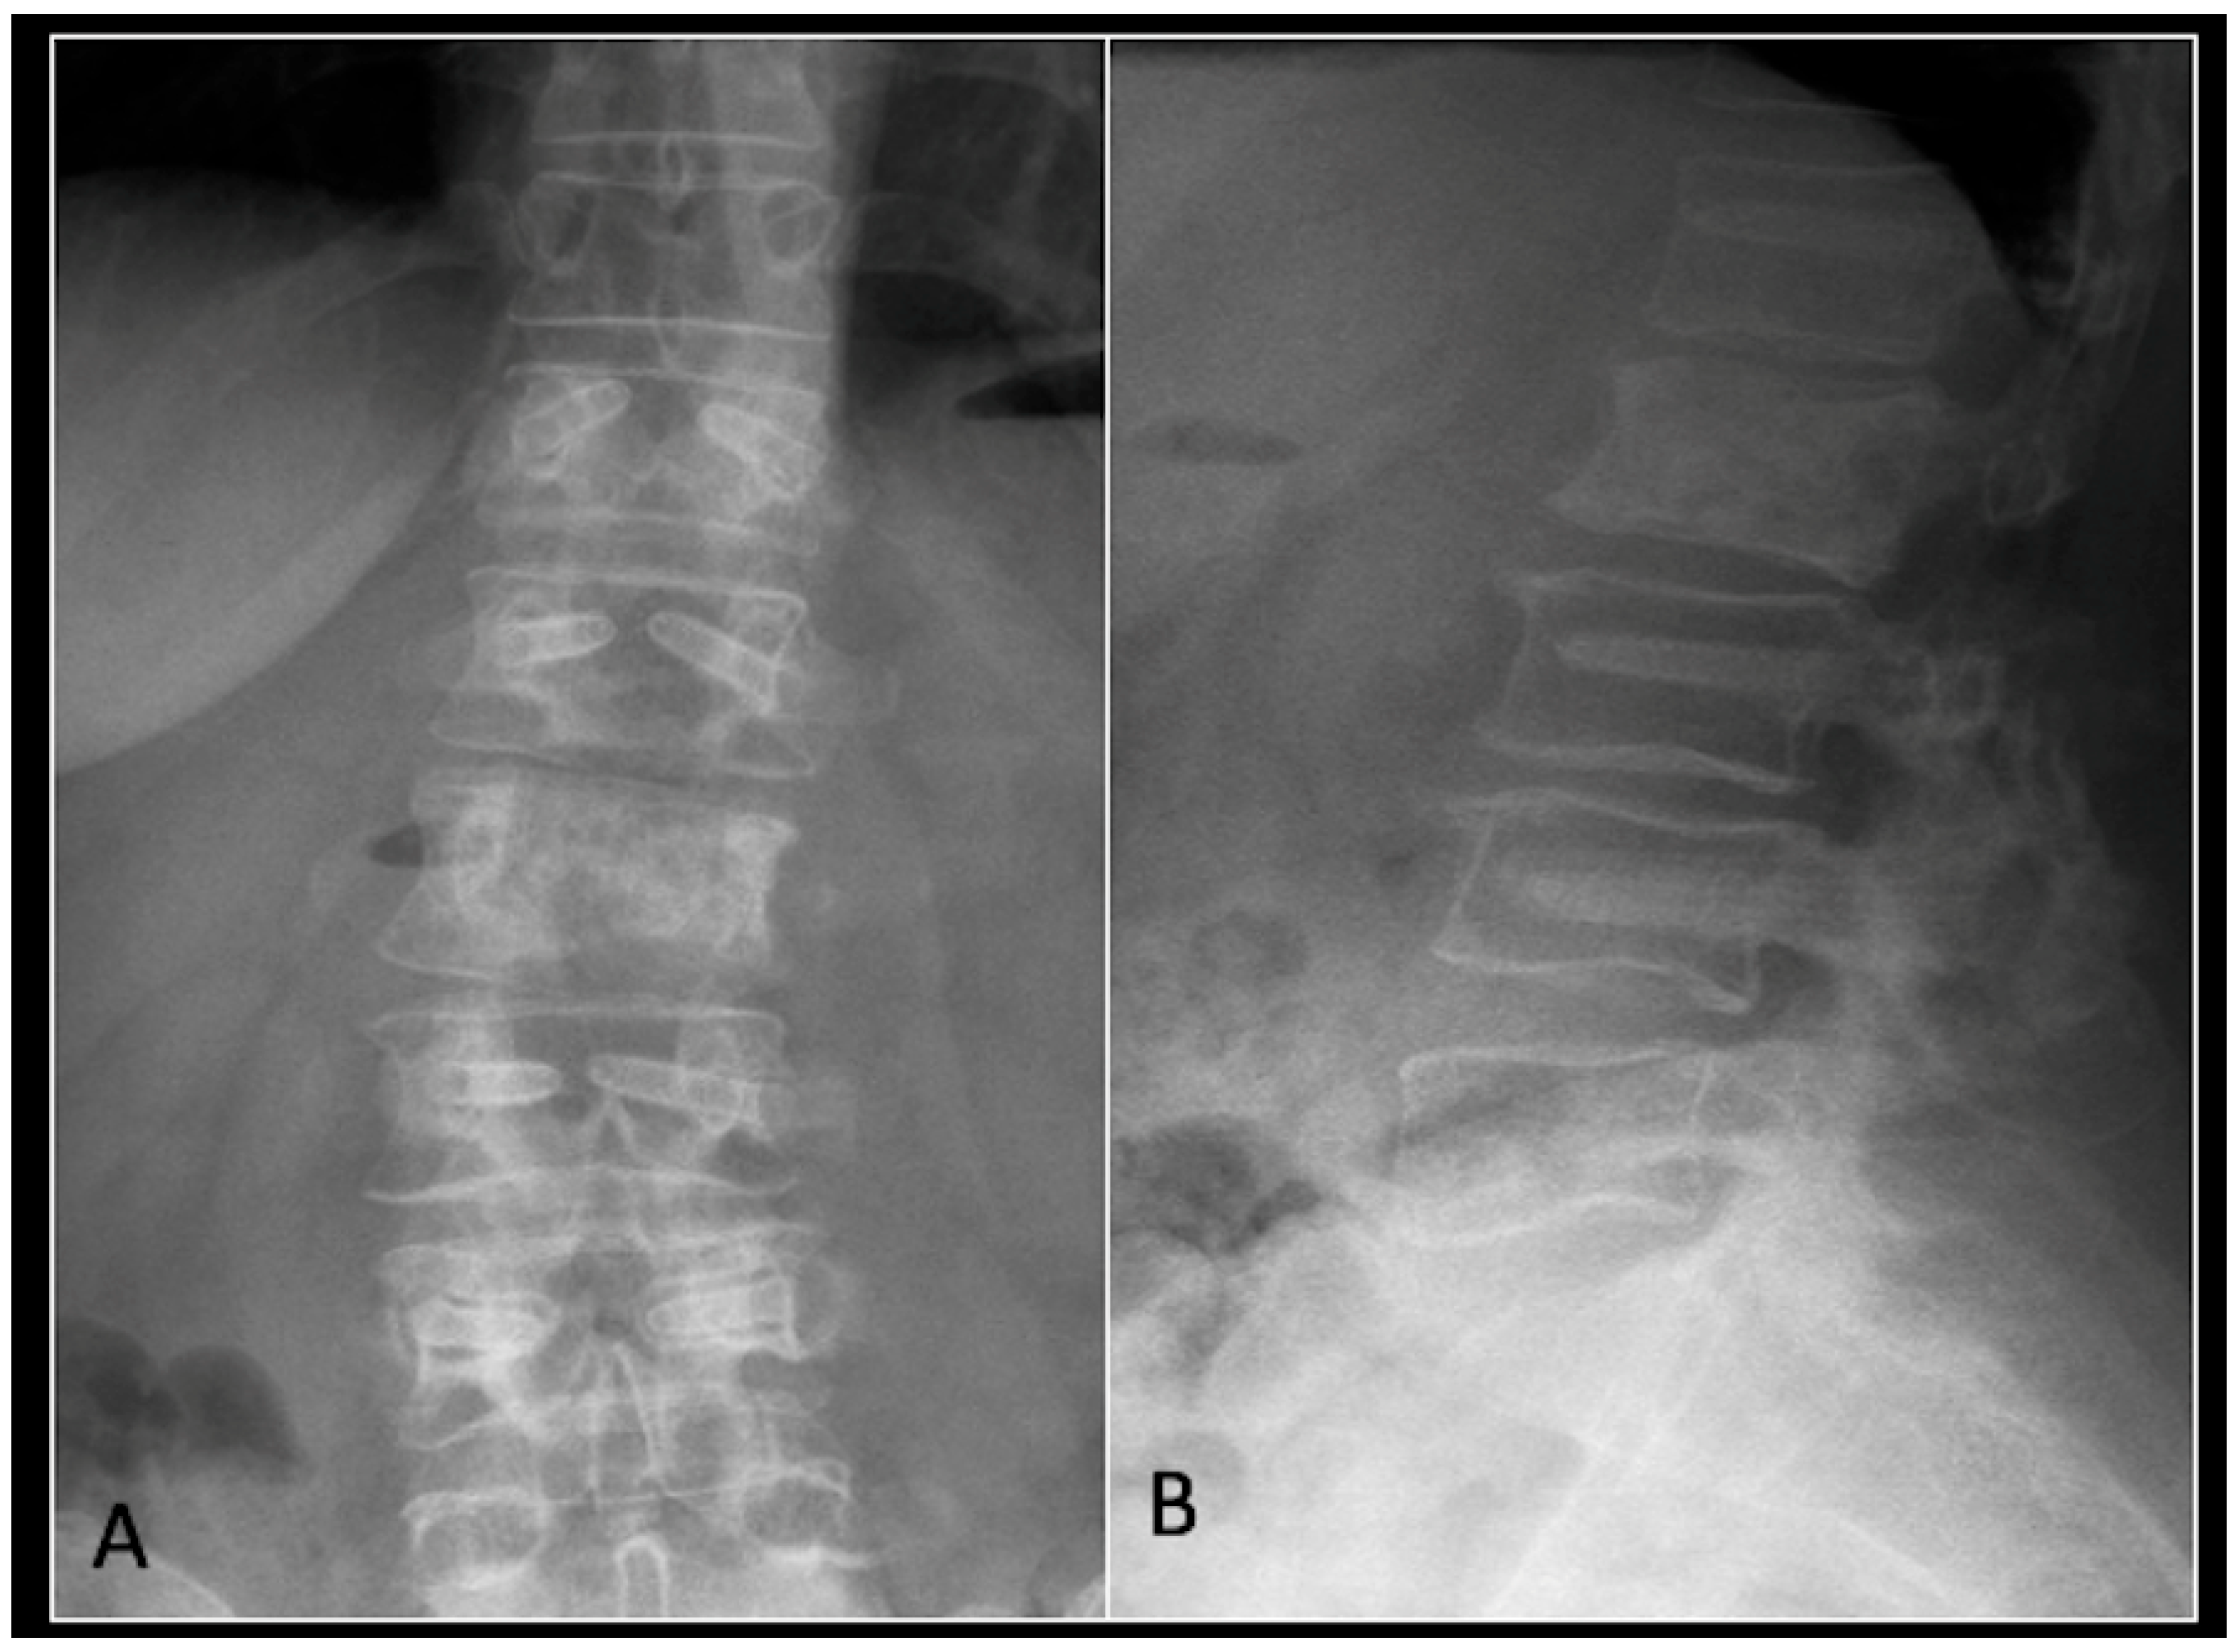

Figure 12.

(A) demonstrates an anteroposterior view, and (B) illustrates a lateral standing radiograph of the lumbosacral spine demonstrating carbon-based posterior instrumentation.